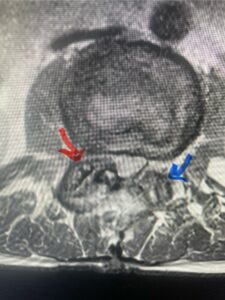

Another patient, a 77 year-old female, presents with pain, numbness, and weakness of her arms and difficulty with balance over a 6-month period. MRI revealed severe osteophytic disease at C5-C7 with cord compression (Fig. 4). Further work-up by fine-cut cervical CT to evaluate the nature of compression revealed a completely calcified osteophyte (Fig. 5). Although the patient had a good lordosis and a posterior cervical approach would accomplish an adequate decompression, we elected to perform a two-level anterior cervical discectomy and fusion. This particular osteophyte is formidable because of its size but the compression was all anterior and would be a less invasive approach. Fortunately, during the procedure, the patient had a fair amount of osteoporosis which allowed the osteophyte to be drilled and bit away with considerable ease. Interestingly, the C6 7 osteophyte which was more a sheet of osteophyte was more challenging to remove. In the end the decompression went well, and we placed two interbody devices filled with bone graft with plates at each level (Fig. 6). The patient had a nice recovery with immediate reduction of pain and numbness. This case demonstrates the importance of recognition of cervical myelopathy in its early stages. A significant reversal of function is generally the rule if the patient has appropriate correlative findings on exam and MRI, particularly with long tract distribution weakness development within a year time period.

Figs 4a: Sagittal and axial T2-weighted cervical MRIs demonstrating large osteophyte worse at C5-6 compressing spinal cord more eccentrically to the left (red arrows)

Fig 4b